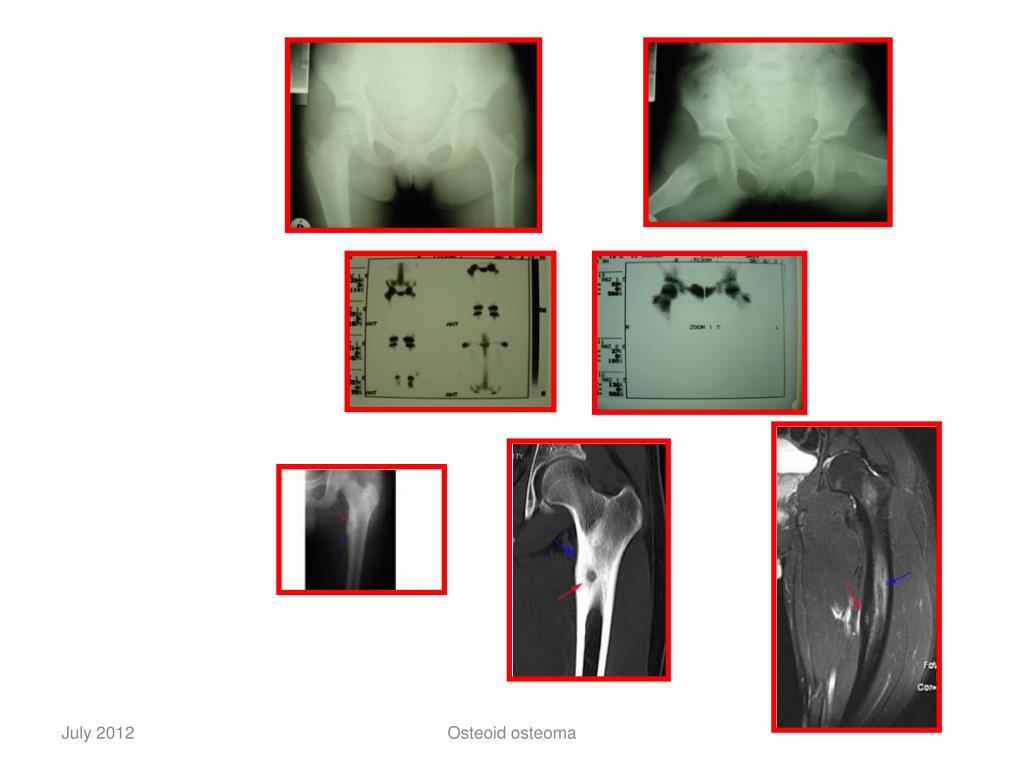

7. RADIOLOGY • Radiolucent nidus • Surrounded by sclerotic bone • Center of nidus may be calcified • Hot spot on Tc - scan Osteoid osteoma

8. Osteoid osteoma